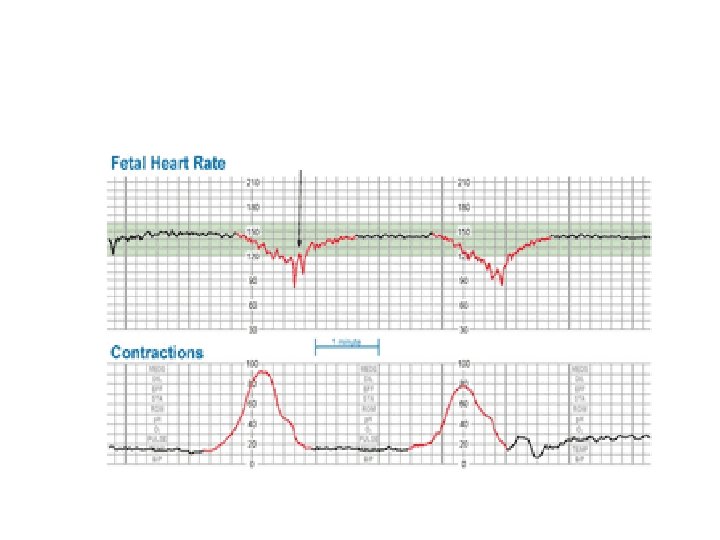

Late Deceleration Gradual decrease in FHR with onset of deceleration to nadir >30 seconds. The nadir of the deceleration occurs after the peak of the contraction

Late Deceleration • Reflex • Myocardial depression